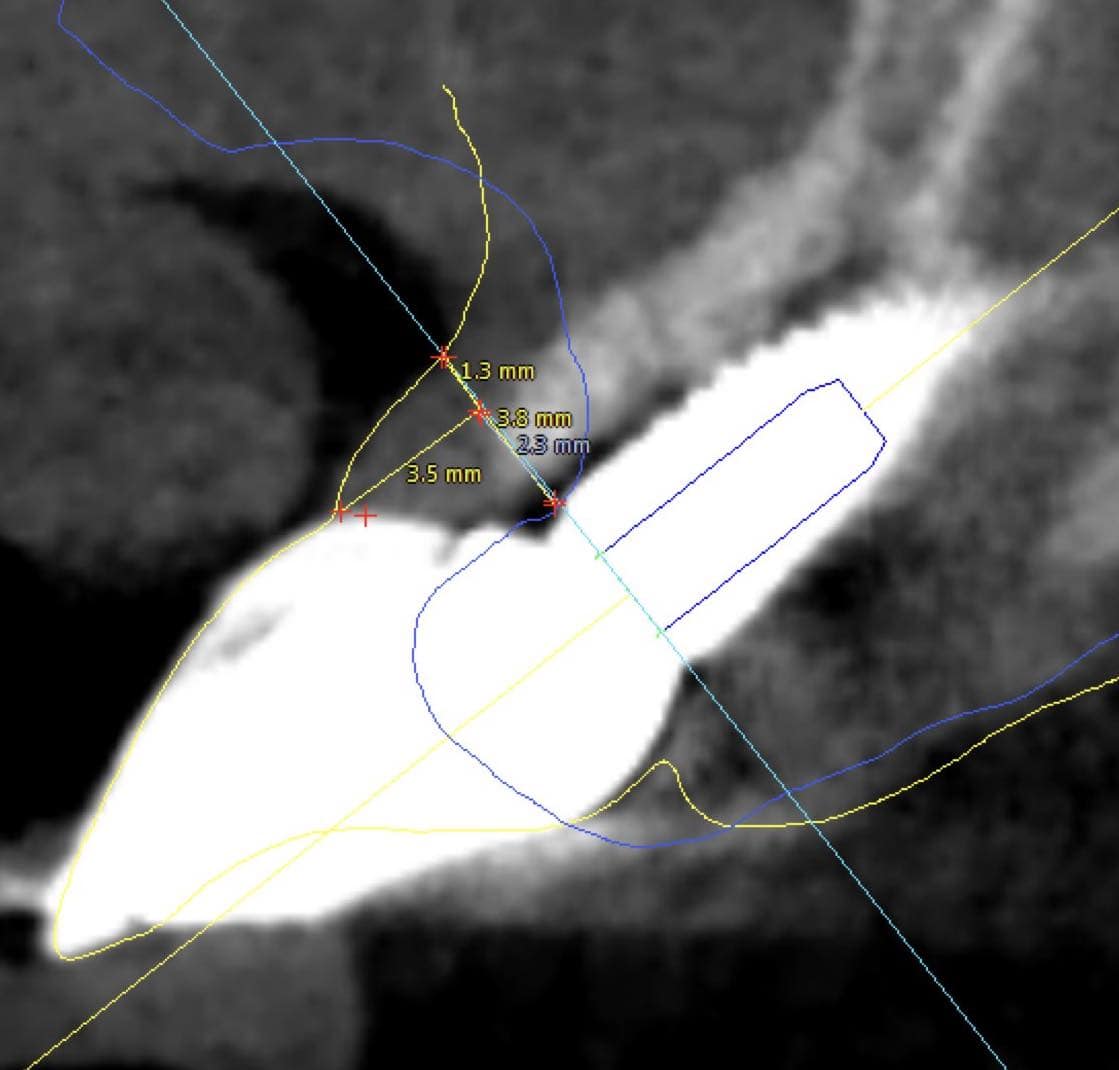

Observe the dimensions of the buccal peri-implant mucosa 18 months after implant placement with Guided Bone Regeneration of a self contained buccal bone defect. The overall mucosa before surgery was actually only 1.3 mm thick, but thanks to the augmentation of the bone, there is sufficient "flat land" to establish a wide base of the pyramid (5.1 mm) and the essential soft tissue height (3.5 mm).It's not a townhouse, it's a pyramid, but will do the job!